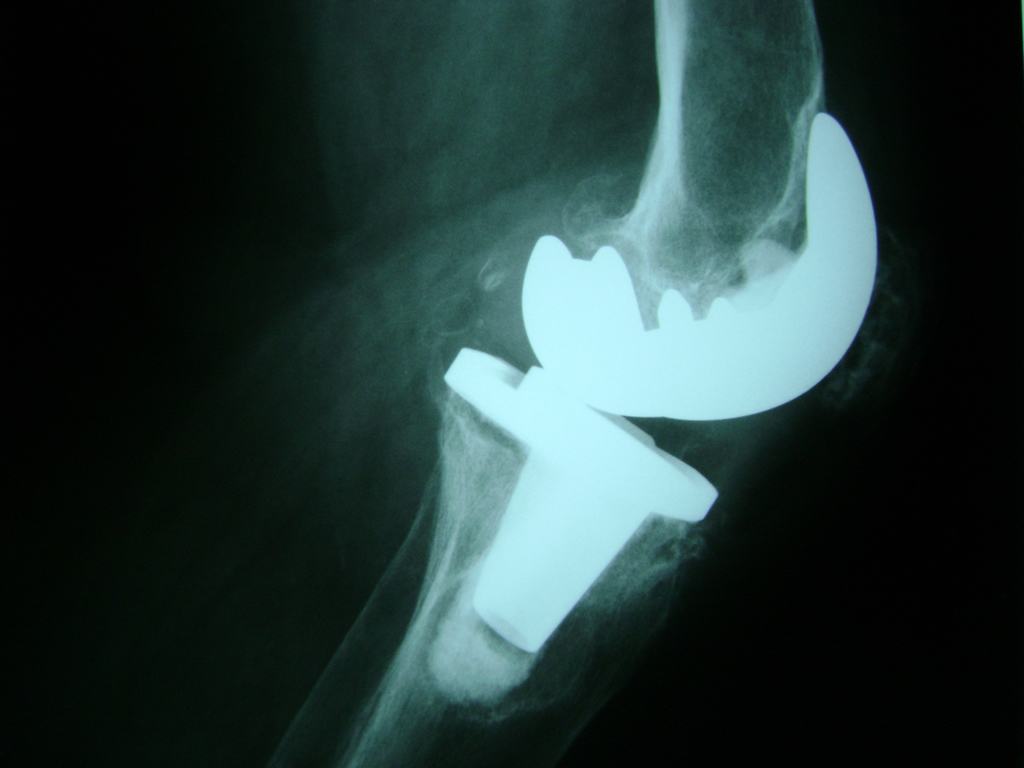

Húmero - Rodilla